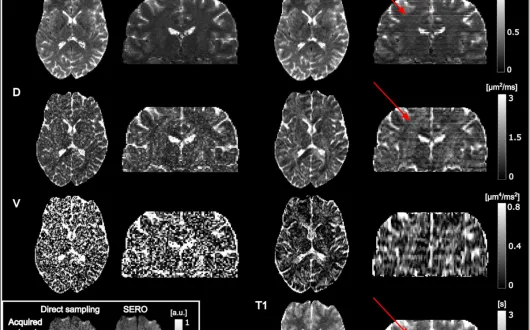

Na to pytanie odpowiada artykuł "Toward Super Resolution Reconstruction of Diffusion-Relaxation MRI Using Slice Excitation With Random Overlap (SERO)", autorstwa Felixa Mortensena, Jakuba Jurka, Jensa Sjölunda, Geraline Vis, Ronniego Wirestama, Malwiny Molendowskiej, Andrzeja Materki i Filipa Szczepankiewicza.